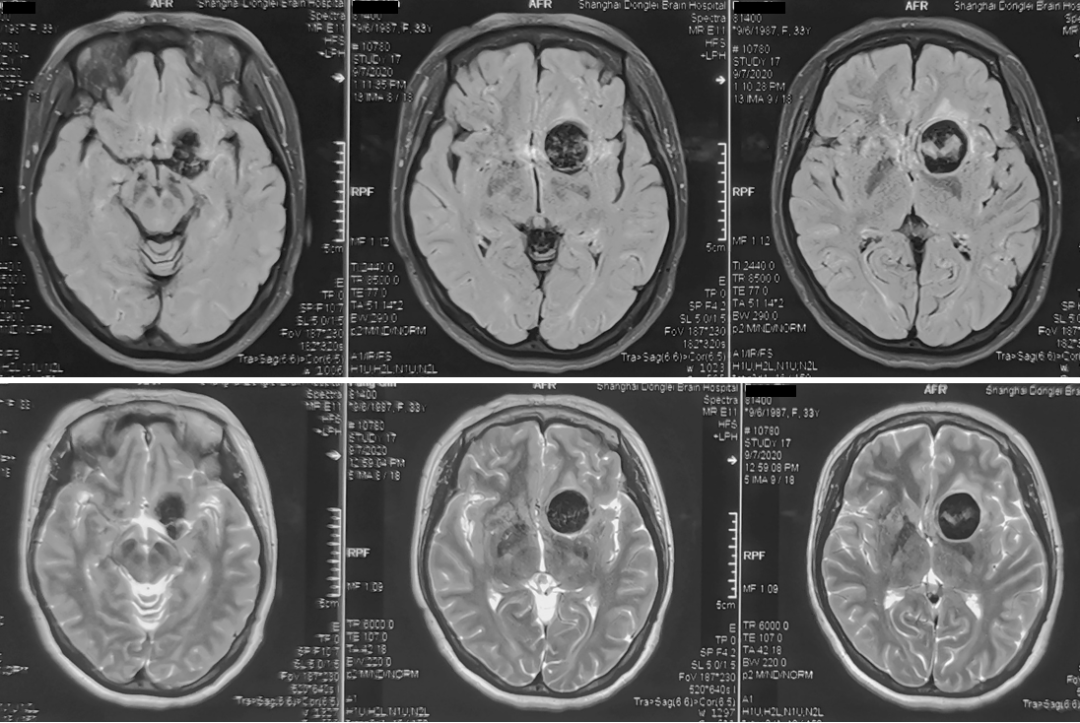

性别:女性,年龄:33 y.o

影像学阳性

术前诊断: